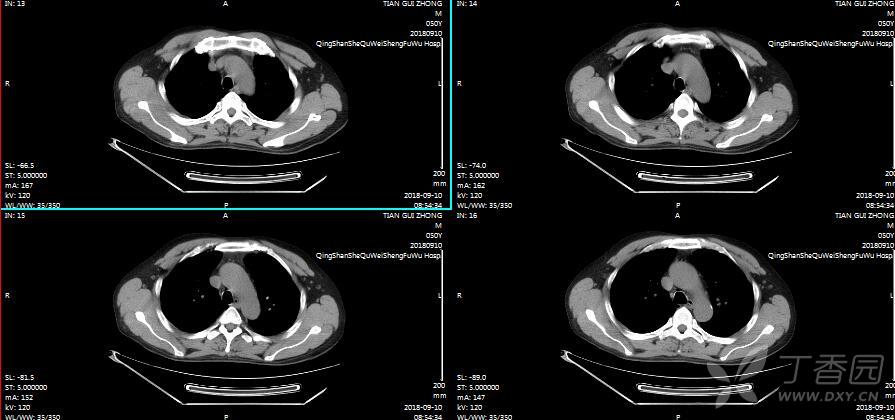

男,50岁,各位老师帮忙看下右肺门,谢谢